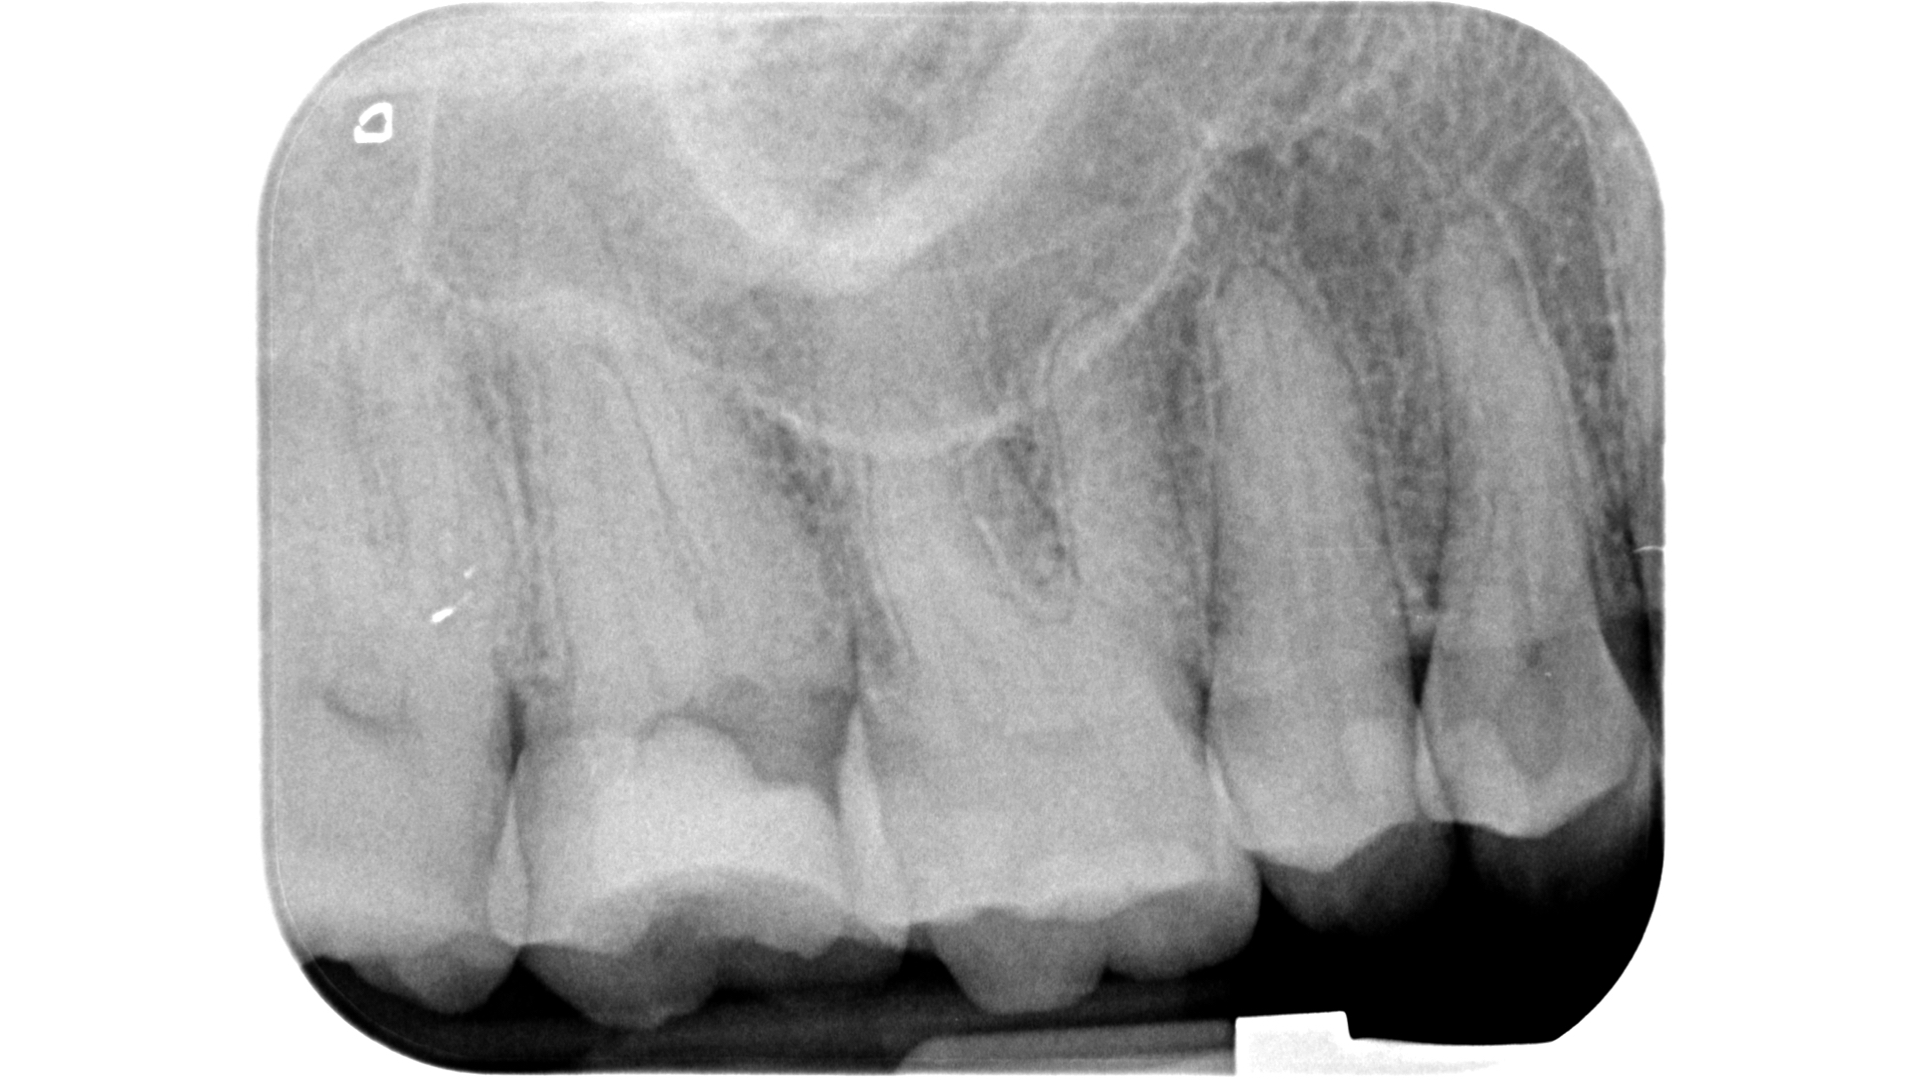

Lo step successivo, ossia l’esplorazione manuale e meccanica del sistema canalare, potrebbe nei casi più complessi essere impedito a causa dell’ostruzione dell’orifizio. Una calcificazione che si estende più in profondità rispetto al pavimento della camera pulpare può infatti rendere impossibile il sondaggio anche con lo strumento più piccolo a disposizione.

Qualora invece l’ostruzione si estendesse più in profondità, la regola della polvere dentinale può servire come guida per il clinico. Questa regola trae il suo fondamento da una delle leggi di Krasner e Rankow7, quella del cambio di colore.

Il sistema canalare è sempre contenuto in un’area più scura rispetto alle pareti canalari e quindi l’azione di avanzamento è guidata proprio da questo assunto cromatico.

Consumando lentamente dentina in direzione apicale (a secco, a basso numero di giri, raffreddando con la siringa ad aria) pochissimi decimi di millimetro per volta si manterrà la corretta centratura all’interno della radice e si potrà visualizzare ad un certo punto una traccia bianca: non si tratta altro che di polvere dentinale prodotta dall’azione dello strumento rotante che si deposita in maggiore quantità proprio in corrispondenza della traccia dell’orifizio.

Lo strumento ideale per avanzare alla ricerca del canale è ancora una volta Endotracer. Il gambo lungo (disponibile anche nella versione 34 mm, oltre che 31 mm) consente di poter avere sempre controllo visivo sull’avanzamento.

I diametri utilizzati vengono scelti in base alla profondità: via via che si procede apicalmente è necessario ridurre il diametro e anche la velocità di utilizzo, oltre che fare pause di controllo sempre più frequenti.

Questa azione di consumo selettivo della dentina può rendere visualizzabile in tempi molto brevi la traccia “bianca” di polvere depositata sull’orifizio; qualora invece i primi passaggi non avessero reso possibile la localizzazione è opportuno alternare irrigazione con ipoclorito di sodio e asciugatura per poi ripartire con un nuovo ciclo di escavazione (Figure 27-33).